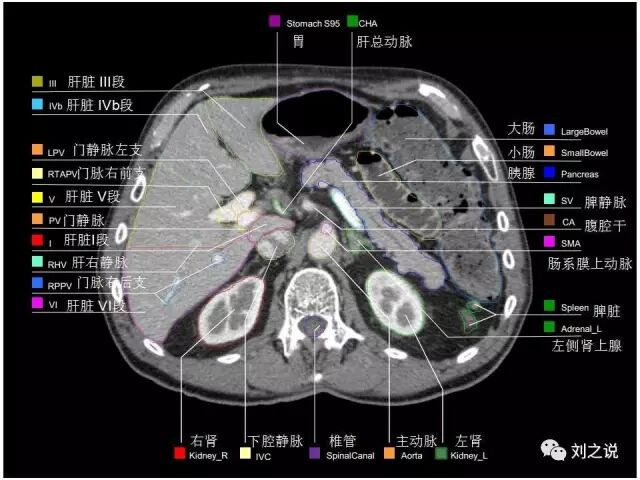

参考RTOG共识和3D-body解剖。

来源:刘之说